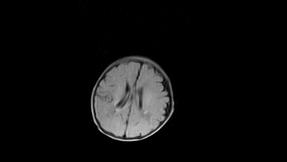

标题: PED3413:患儿女6天体检

缺血缺氧性脑病

6天为新生儿,髓鞘发育正常;左侧颞顶叶蛛网膜下腔增宽,请结合临床。

1。缺血缺氧性脑病2。左侧颞顶叶外部性脑积水,可观察

半卵圆中心上方层上可见对和乐大脑皮质t1高信号,考虑有hie可能,不知有何症状,建议加做dwi及复查

符合缺氧缺血性脑病影像表现。